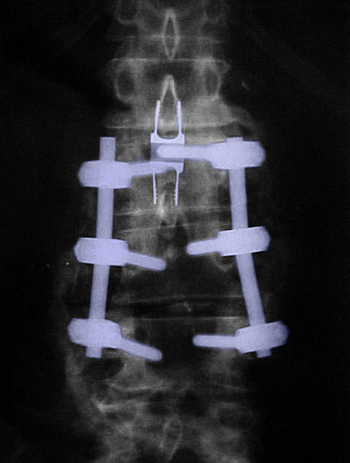

Περιγραφή Η οσφυϊκή σπονδυλοδεσία πραγματοποιείται με γενική αναισθησία, με τον ασθενή σε πρηνή θέση και υπό ακτινοσκοπικό έλεγχο. Η τομή δέρματος γίνεται στο μέσο της ράχης, επί των σπονδύλων που πρόκειται να συνδεθούν. Τα οπίσθια στοιχεία τους παρασκευάζονται και κατόπιν τοποθετούνται βίδες από κράμα τιτανίου στα σώματα των σπονδύλων (2 σε κάθε ένα). Οι κεφαλές των βιδών συνδέονται με ράβδους και έτσι επιτυγχάνεται συνένωση των σπονδύλων σε μία κινητική μονάδα αφού προηγουμένως έχει γίνει ανάταξη της διαταραχής της ανατομίας, (αν αυτή προϋπάρχει όπως στη σπονδυλολίσθηση ή τα κατάγματα) με τη βοήθεια ειδικών εργαλείων. Η σπονδυλοδεσία συμπληρώνεται με τοποθέτηση οστικού μοσχεύματος γύρω από το σύστημα σπονδυλοδεσίας προκειμένου να επιτευχθεί αργότερα (σε ορίζοντα μηνών) σταθεροποίηση της σπονδυλικής στήλης μέσω οστεοσύνθεσης, δηλαδή δημιουργίας νέου οστού το οποίο συνενώνει τους σπονδύλους. Αυτό είναι και ο τελικός σκοπός της επέμβασης. Η ανωτέρω περιγραφόμενη μέθοδος ονομάζεται οπίσθια σπονδυλοδεσία με διαυχενικές βίδες και ράβδους και γίνεται συχνά σε συνδυασμό με οσφυϊκή πεταλεκτομή για να αποσυμπιεστούν τα νευρικά στοιχεία που πιέζονται από την εκφυλιστική νόσο, το κάταγμα ή τον όγκο της σπονδυλικής στήλης. Μια άλλη μέθοδος σπονδυλοδεσίας, με την ίδια οπίσθια προσπέλαση, είναι η τοποθέτηση μεσοσπονδυλίων εμφυτευμάτων τύπου PLIF, η οποία όμως απαιτεί πάντα οσφυϊκή δισκεκτομή γιατί η τοποθέτηση τους γίνεται στη θέση του αφαιρεθέντος μεσοσπονδύλιου δίσκου. Τα εμφυτεύματα αποτελούνται από τιτάνιο ή ειδικό πολυμερές πλαστικό και χρήζουν και αυτά συνοδεία οστικού μοσχεύματος για να επιτευχθεί οστεοσύνθεση. Η δυνατότητα ανάταξης ανατομικής διαταραχής και σταθεροποίησης είναι όχι μεγάλη με τη βοήθεια αυτής της μεθόδου και γι' αυτό συνδυάζεται συχνά με οπίσθια διαυχενική σπονδυλοδεσία. Η πρόσθια οσφυϊκή σπονδυλοδεσία, με προσπέλαση μέσω της κοιλιακής χώρας, χρησιμοποιείται σπανιότερα, και κατά κανόνα σε ασθενείς με βαριά ανατομική προβληματική συμπεριλαμβάνουσα και τα σπονδυλικά σώματα. Αντενδείξεις και επιπλοκές Οι αντενδείξεις της οσφυϊκής σπονδυλοδεσίας δεν είναι πολλές. Οι σημαντικότερες είναι η κακή ποιότητα οστού, όπως στην προχωρημένη οστεοπόρωση, η οποία καθιστά την ενσφήνωση των βιδών στο σπονδυλικό σώμα επισφαλή και κατ' επέκταση το σύστημα σπονδυλοδεσίας επιρρεπές σε αστοχίες, και η ενεργός λοίμωξη. Οι επιπλοκές της οσφυϊκής σπονδυλοδεσίας είναι συχνότερα παθολογικού χαρακτήρα όπως η πνευμονική λοίμωξη και η θρόμβωση των κάτω άκρων και σπανιότερα χειρουργικές όπως η αποτυχία συνοστέωσης και ο τραυματισμός της μήνιγγας ή/και των οσφυϊκών νεύρων. |

Οσφυϊκή σπονδυλοδεσία Ο3-Ο5. Βίδες στα σώματα των σπονδύλων (πράσινο βέλος) ενωμένες με ράβδους (φούξια βέλος). Συνδετική γέφυρα με κυανό βέλος.Περιοχή της πεταλεκτομής με κόκκινο περίγραμμα. |